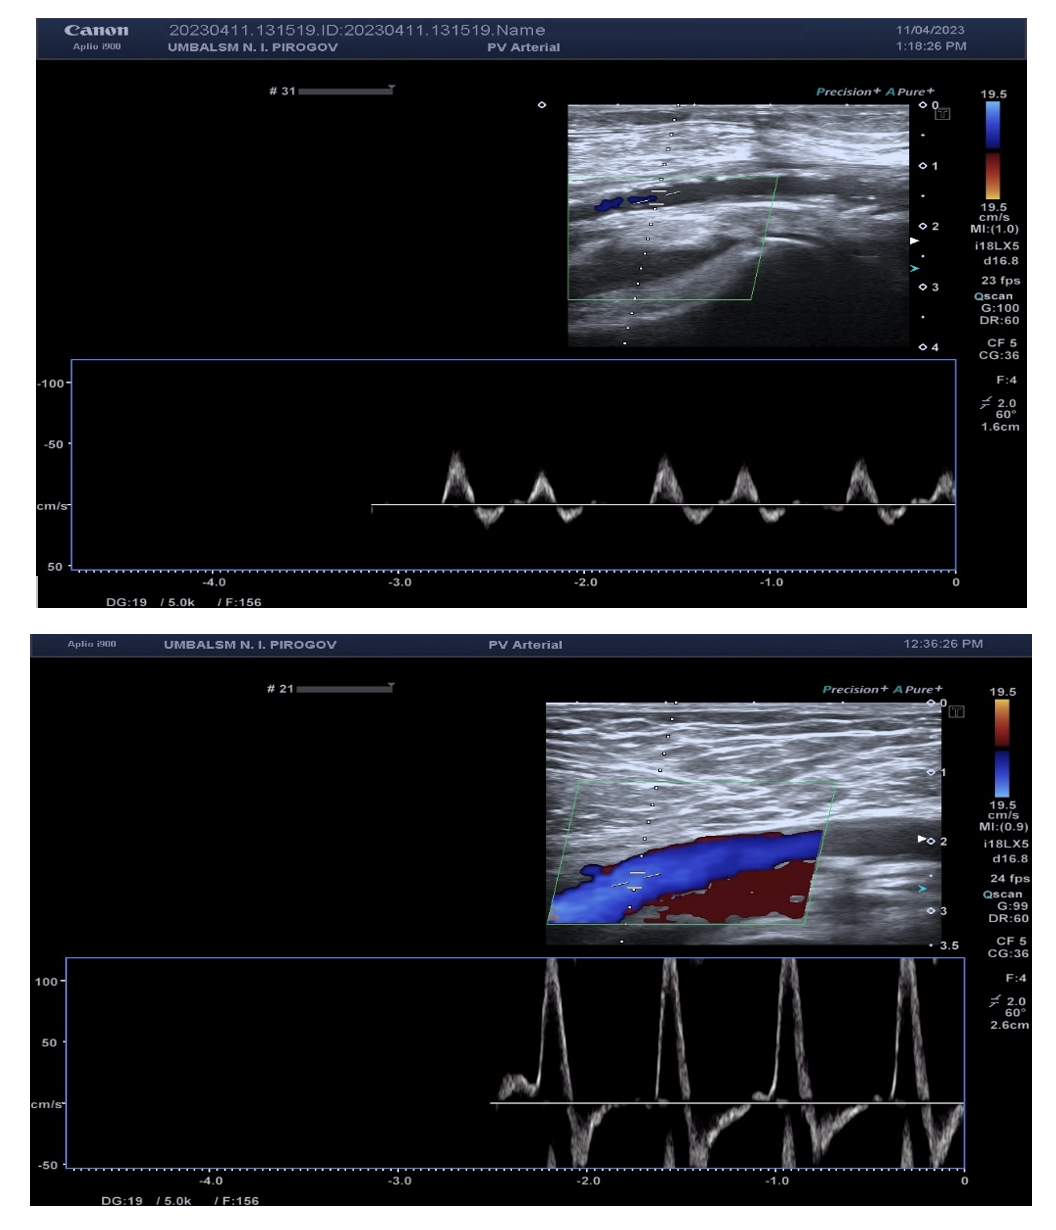

The patient was discharged after 3 days. She returned 15 and 30 days later for a planned Doppler sonography, which objectified the preserved result of the EVT of the right axillary, brachial, radial, femoral, popliteal, and posterior tibial arteries (Figures 13A-C).